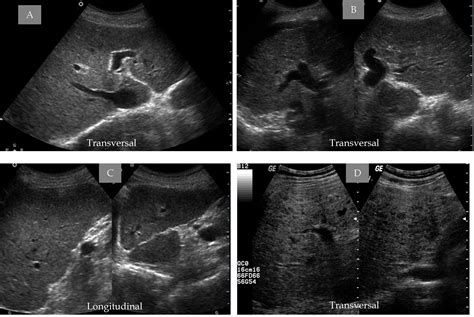

In the field of medical ultrasound imaging, interpreting the visual data displayed on a screen requires a deep understanding of tissue composition. When a radiologist or sonographer examines an organ, they are looking for specific patterns of brightness and texture. One of the most critical observations made during these examinations is identifying whether a tissue appears uniform or varied. The phrase Echotexture Is Heterogeneous serves as a fundamental descriptor in diagnostic ultrasound, indicating that the internal structure of an organ or a mass is non-uniform, consisting of various components that reflect sound waves differently.

Echotexture refers to the appearance of the internal structure of an organ or tissue as it is depicted by ultrasound. Sound waves generated by the transducer penetrate the body, bounce off various structures, and return to the receiver. These echoes are converted into the grayscale images we see on monitors. When an area is described as having homogeneous echotexture, it means the echoes are uniform in intensity, suggesting a smooth, consistent internal structure like that of a healthy liver or thyroid. Conversely, when we say Echotexture Is Heterogeneous, we are noting that the tissue contains a mix of echoes—some bright (hyperechoic), some dark (hypoechoic), and some fluid-filled (anechoic).

A heterogeneous pattern is often the first visual cue that something abnormal may be occurring within the tissue. While some structures are naturally heterogeneous due to their complex anatomy, a sudden shift from a homogeneous appearance to a heterogeneous one in a follow-up scan is a significant clinical indicator that often warrants further investigation, such as biopsy or advanced imaging.

When a report states that Echotexture Is Heterogeneous, the clinical path forward depends heavily on the organ being examined. For example, a heterogeneous thyroid gland may be a sign of Hashimoto’s thyroiditis, an autoimmune condition. In the liver, heterogeneity might suggest cirrhosis or fatty liver disease. Because the term describes a wide spectrum of possibilities, it is almost never used as a standalone diagnosis.